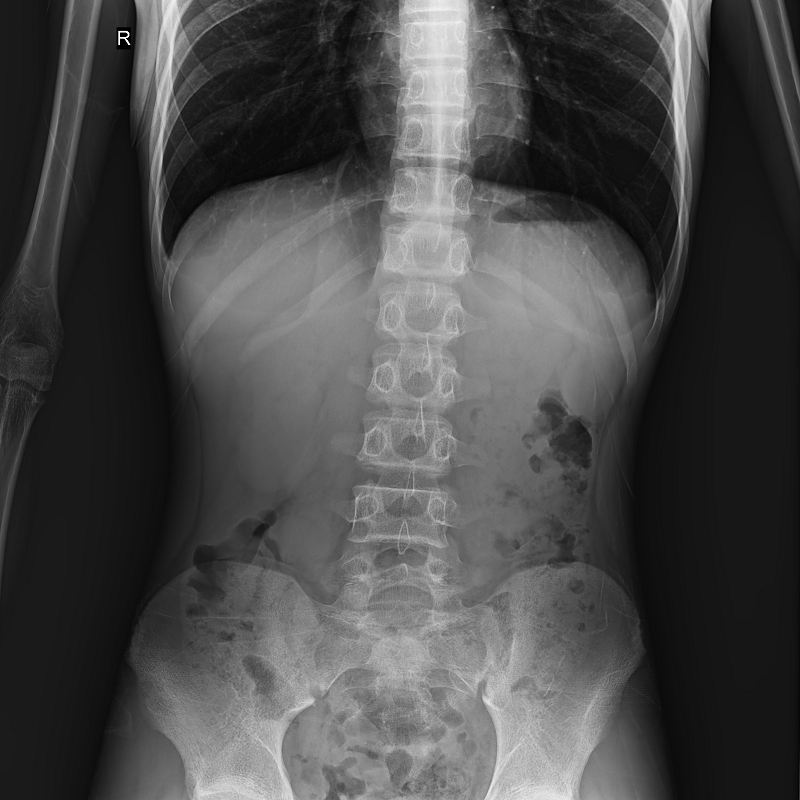

● 圖像拼接

系統(tǒng)可以識(shí)別曝光圖像,無需設(shè)置識(shí)別點(diǎn)即完成精準(zhǔn)拼接,呈現(xiàn)大范圍完整影像。